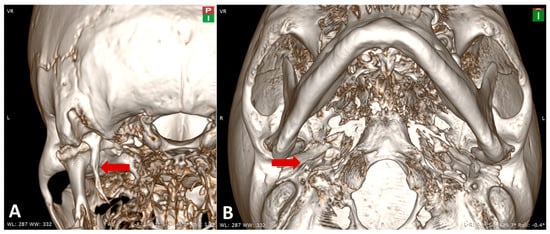

| Anatomical landmarks | MPR reconstruction using the orbito-meatal sagittal plane, with oblique adjustment in the axial plane. Length: 33 mm measured in the coronal plane. |

| Reference planes | Dimensional assessment from the inferior surface of the petrous part of the temporal bone |

| 3D Model | 3D reconstruction—length: 31.2 mm |